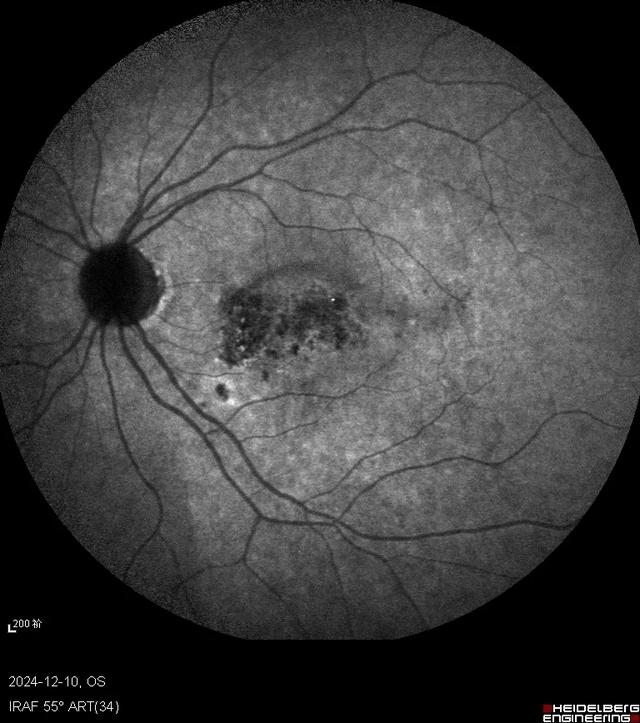

自发荧光右眼

自发荧光左眼

马上对此患者进行了抽血检查来判断是否存在梅毒感染,另外还安排了眼底荧光素血管造影(FFA)和吲哚菁绿(ICG)造影检查。因为我们知道梅毒是“模仿大师”,可以引起视神经炎、视网膜血管炎、脉络膜炎等多种眼底改变。很快造影结果就出来了,右眼FFA黄斑早期高荧光,晚期高荧光衰减;而ICG则早期低荧光,晚期高荧光;左眼FFA黄斑渗漏较右眼明显,ICG晚期也是表现为高荧光。双眼自发荧光类似,表现为中央低荧光,围绕一圈周围高荧光。果不其然,符合这时候梅毒性后极部鳞状脉络膜视网膜炎的临床表现。

梅毒性后极部鳞状脉络膜视网膜炎的临床特征包括青壮年、急性双眼起病、视力下降显著而眼部体征较轻。OCT上黄斑区椭圆体带不同程度损伤伴有RPE结节和玻璃体细胞。自发荧光、FFA、ICG、眼底彩照表现为后极部累及黄斑区鳞片状或弥漫性病灶。在临床分析中,要抓住点点滴滴的蛛丝马迹,往往一些容易被忽略的小问题最后会成为“破案”的钥匙,借此病例,与眼科同道们共勉!